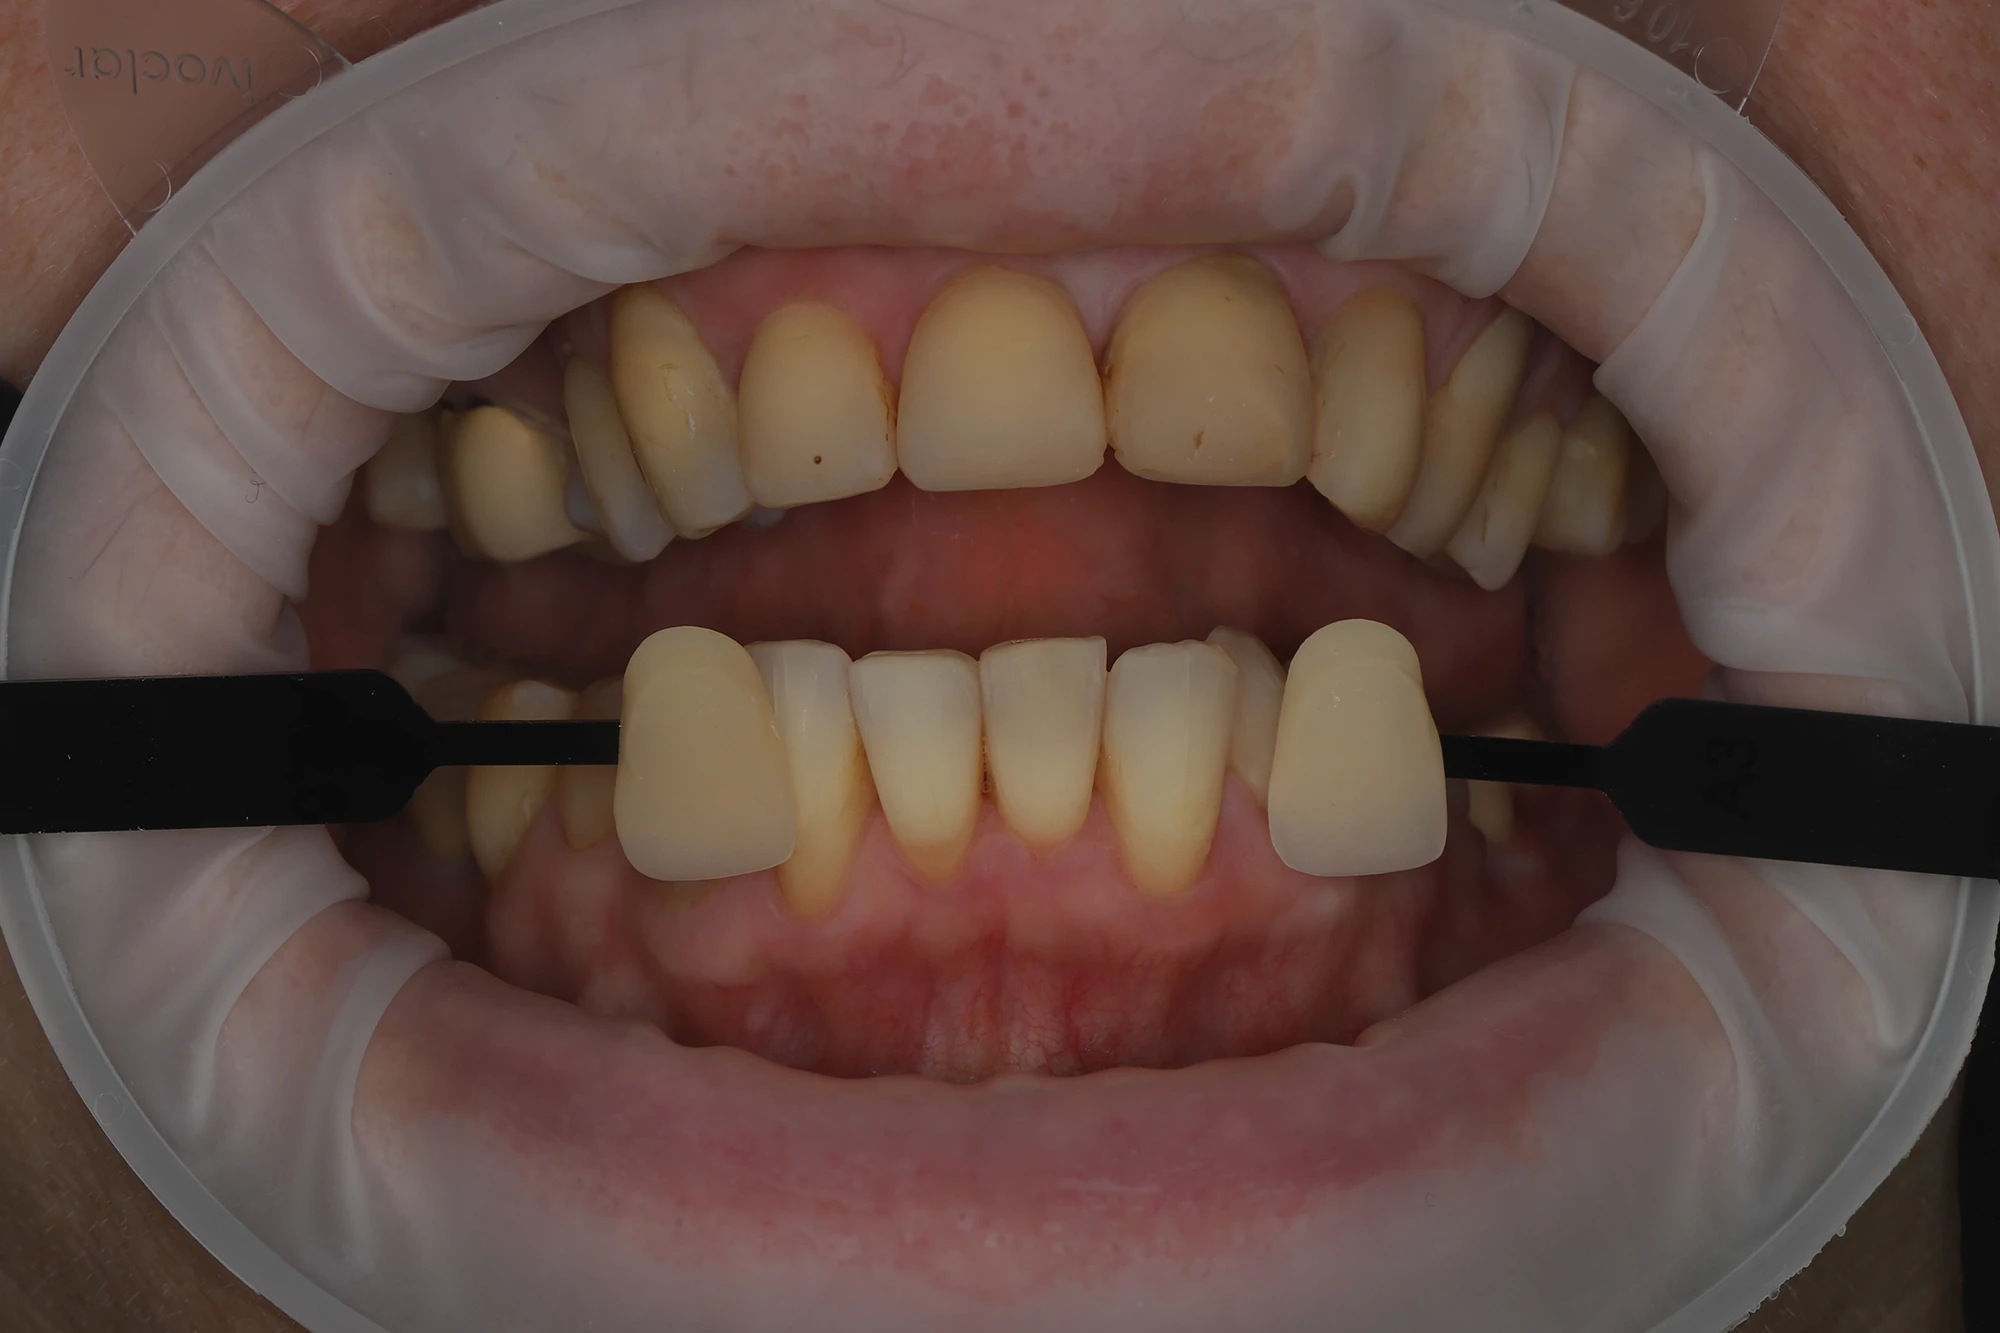

Пациентка хотела решить проблему только локально и попросила запротезировать ее в привычной окклюзии. Был проведен фотопротокол и сделан цифровой оттиск, которые отправлены в лабораторию.

Во время визита пациентки в клинику были проверены посадка ортопедических реставраций, их краевое прилегание, окклюзионные контакты, симметрия и эстетическая составляющая. Пролечен контактный и пришеечный кариес на 33 зубе. Коронки на имплантатах зафиксированы винтовым способом, на своих зубах — на стеклоиономерный цемент.